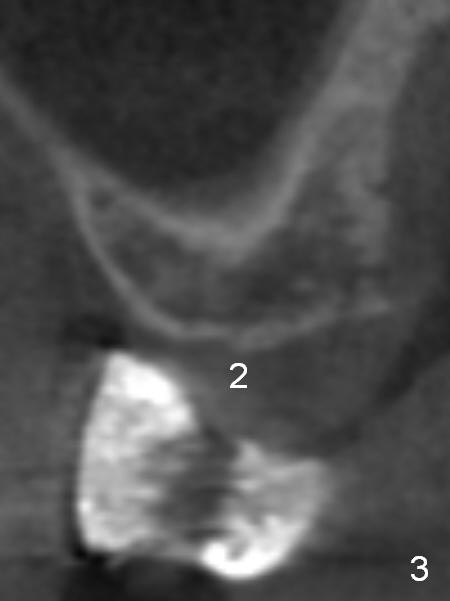

A 49-year-old lady has lost #2-4 for quite a while (Fig.1, no indication for antibiotic study (for cases with <6 months post extraction)). Bone height at #2 and 3 is limited. Use a 2 mm pilot drill to start osteotomy with rubber stopper at 4 mm, followed by insertion of 2 short parallel pins (PP) at #2 and 3 (Fig.2,4,6,8). The PPs may be not stable because of shortness. At #4 (8 mm initially), insert a marked PP for PA. If the position and trajectory of each osteotomy is correct, use trephine burs for further osteotomy at #2,3, since they have labels of 2,4,6 mm. For example small one at 4 mm, larger one at 6 mm. If the bone stays in place after trephine bur usage, use Bicon osteotomes to do sinus lift. Allograft and Osteogen is to be loaded in small syringes (x4). Previous implant surgeries indicate that the bone density of the maxilla is high (1,2). CT shows variable density (compare Fig.1 vs. 2, 3 vs. 4 et al). The density at the medulla is low; that at the cortices high. The patient plans to have 2 implants. If the implant at #3 is not stable, the implant at #2 will be needed for splinting.